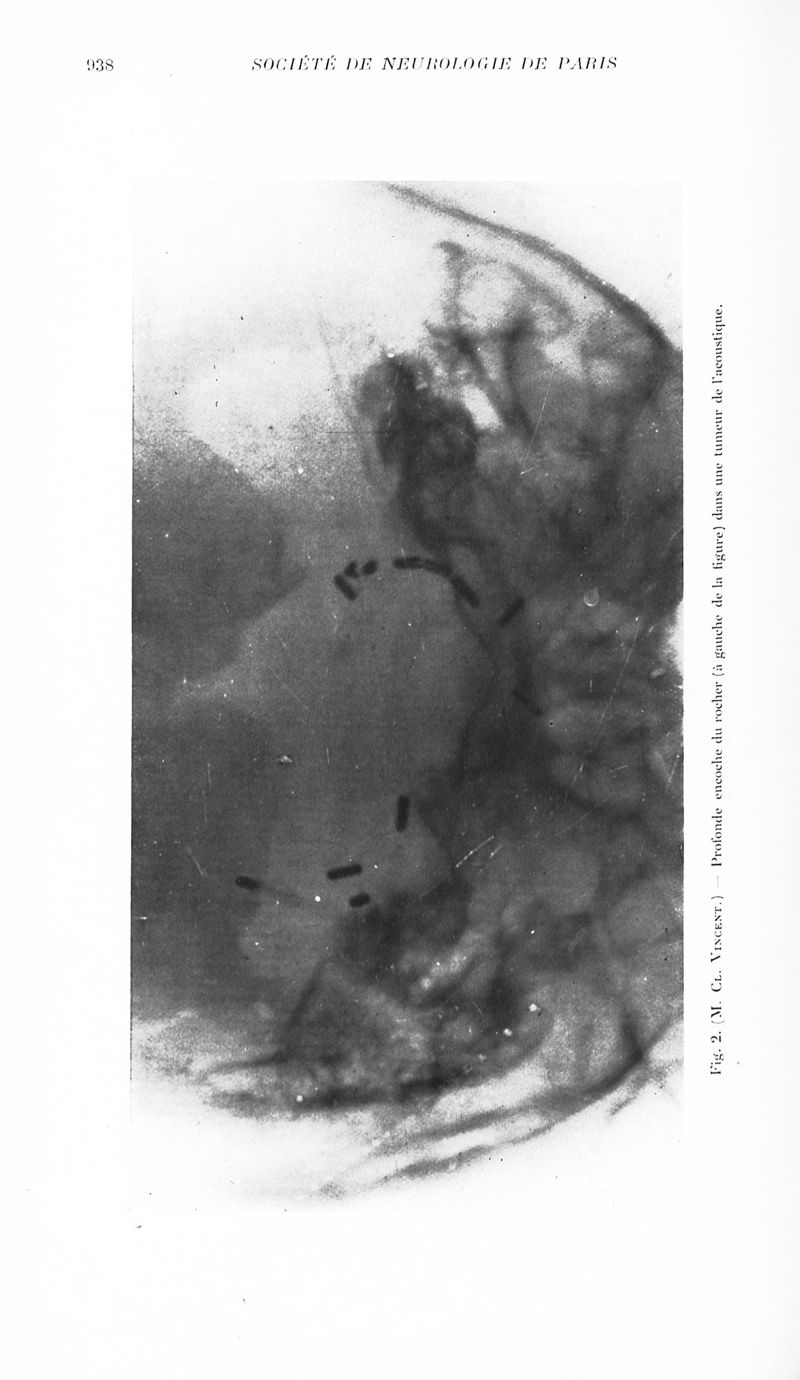

Revue neurologique

1935, vol 2. - Paris : Masson , 1935.